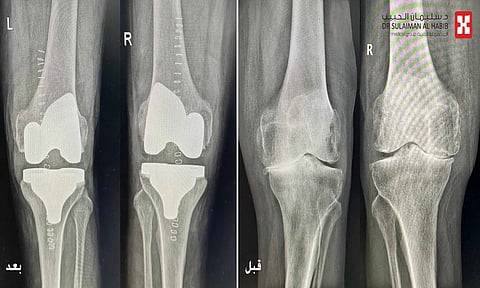

ذكر ذلك أ.د. الدكتور فوزي الجاسر؛ استشاري جراحة العظام والمفاصل، رئيس الفريق الطبي المعالج، الحاصل على البورد الكندي، الذي أضاف أن الفريق الطبي استمع لشكوى المراجع، واطلع على ملفه الطبي، وأخضعه لفحوصات دقيقة عدة، شملت التصوير بالأشعة السينية الرقمية (Digital X-rays)، والتحاليل المخبرية، وأوضحت النتائج وجود ميلان في الساقين وخشونة شديدة من الدرجة الرابعة في مفصلَي الركبة.

وأوضح، أن المراجع تمّ تقييمه من قبل استشاريي القلب والتخدير، حيث أُجريت له مجدّداً بعض الفحوصات القلبية الدقيقة، مع إعطائه بعض العلاجات اللازمة، وبعد التأكّد من أهليته الصحية، خضع لعملية استغرقت ساعتين تحت التخدير النصفي، تمّ فيها تعديل ميلان الساقين، وتغيير مفصلَي الركبتَيْن بنجاح.